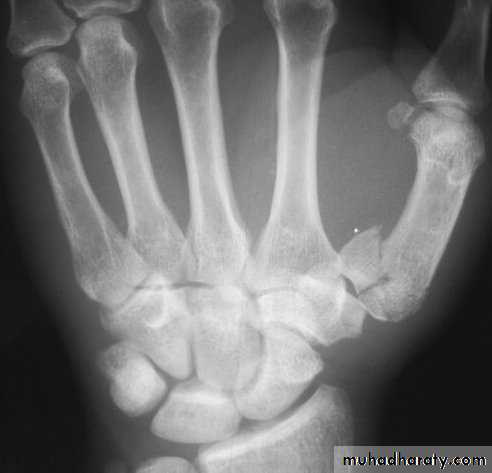

Metacarpal fractures:

Fracture of metacarpal shaft: transverse or spiral

Fracture of the metacarpal neck: usually of the 5th finger (boxer's fracture), localized swelling with flattening of the knuckle.Fracture of the metacarpal base.